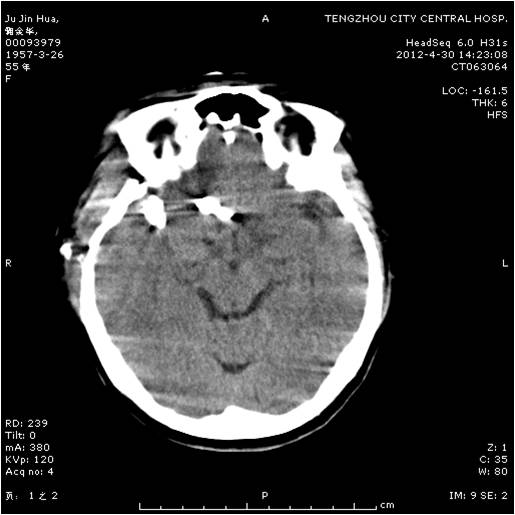

動脈瘤夾閉術(shù)前 動脈瘤夾閉術(shù)后

垂體瘤術(shù)前 垂體瘤術(shù)后